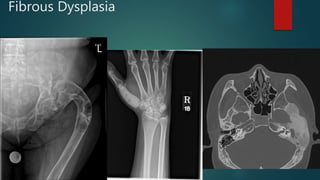

Fibrous Dysplasia

Hyperostosis frontalis interna